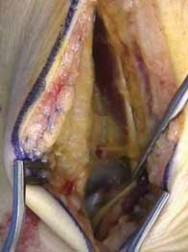

1. Reconstruction of talar body fractures is best performed using dual medial and anterolateral approaches with the addition of the medial malleolar osteotomy.

1.

Unless the fracture line is transverse and very anterior, allowing reasonable access by a standard dual approach, a transmalleolar approach is planned.

2.

Fracture patterns to the body of the talus occur in both sagittal and coronal planes. Regardless of the fracture plane, the principle is to work through the fenestration provided by the medial malleolar osteotomy, using fine-tipped dental probes, reducing the posterior portion of the body to the anterior body fragments.

36.

Small, smooth Kirschner wires are inserted from medial and lateral portals, provisionally fixing the body.

37.

Associated fractures of the neck of the talus are provisionally fixed after reduction of the body fracture.

Interfragmentary, countersunk, mini-screws (2.7 or 2.0 mm) are sequentially inserted, fixing the body fragment.

Headless screws can also be used for this fracture.

Finally, countersunk, interfragmentary small fragment (3.5 mm) screws or mini-plate and screw constructs are used to fix the talar neck fracture ( TECH FIG 3).